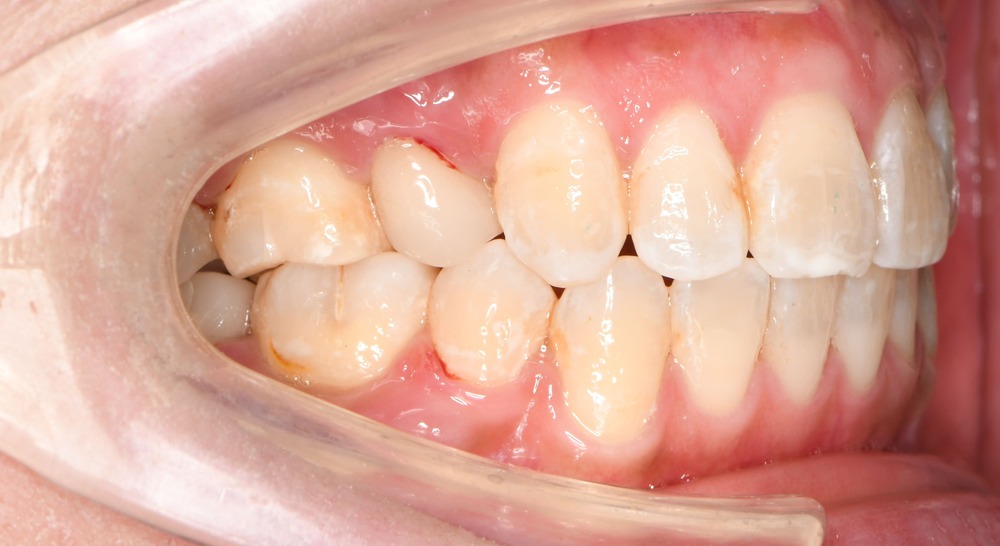

右側

大臼歯の反対咬合が改善し、正常な咬合関係を獲得しました。

患者さまにも大変ご満足いただけました。